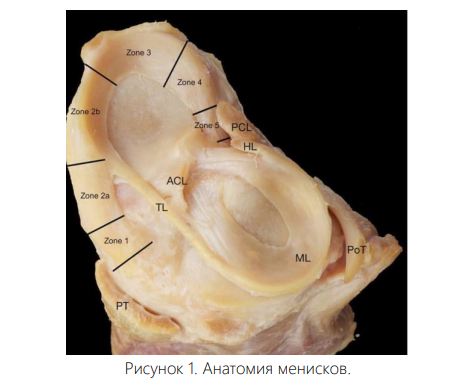

Медиальный и латеральный мениски — это серповидные фиброзно-хрящевые структуры, которые занимают от половины до двух третей площади тибиального плато. Их главная задача заключается в передаче нагрузки через тибиофеморальный сустав. Это снижает давление на окружающий суставной хрящ и способствует долговременному сохранению целостности сустава [6]. Менисковые корни играют ключевую роль, фиксируя мениски к передней и задней частям тибиального плато. Эти прикрепления выполняют важную биомеханическую функцию, преобразуя осевые нагрузки в кольцевые напряжения, предотвращая выпячивание мениска и поддерживая нормальную кинематику коленного сустава [4, 5].

Корни мениска. Анатомия корней мениска хорошо изучена. Каждое из четырех мест их прикрепления отличается по естественной прочности и площади контакта. Передний медиальный (ПМ), задний медиальный (ЗМ) и задний латеральный (ЗЛ) корни содержат центральные пучки волокон, а также дополнительные связывающие элементы.

Передний латеральный (ПЛ) корень переплетается с передней крестообразной связкой (ПКС), перекрывая её и проходя под точкой её прикрепления к большеберцовой кости. Этот корень однороден по всей длине, без дополнительных прикрепляющихся волокон. Суставной хрящ. Суставной хрящ состоит из коллагена II типа и обладает высокоорганизованной структурой [15]. Повреждение этого хряща при травме корня мениска — не редкость. При этом риск травмы выше при остром повреждении латерального корня по сравнению с дегенеративным разрывом медиального корня [6]. Бессосудистая природа суставного хряща ограничивает его способность к заживлению, и в настоящее время активно изучаются методы восстановления для устранения негативных последствий его повреждения. Кроме того, потеря кольцевых напряжений, вторичная к разрыву корня, создает сверхфизиологические нагрузки на хрящ колена. Эти факторы повышают риск развития ОА и необходимости тотального эндопротезирования коленного сустава (ТЭКС) [9, 15].